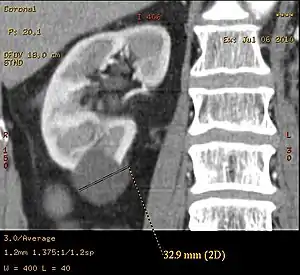

Bosniak II cyst at the lower pole of right kidney with septations within.